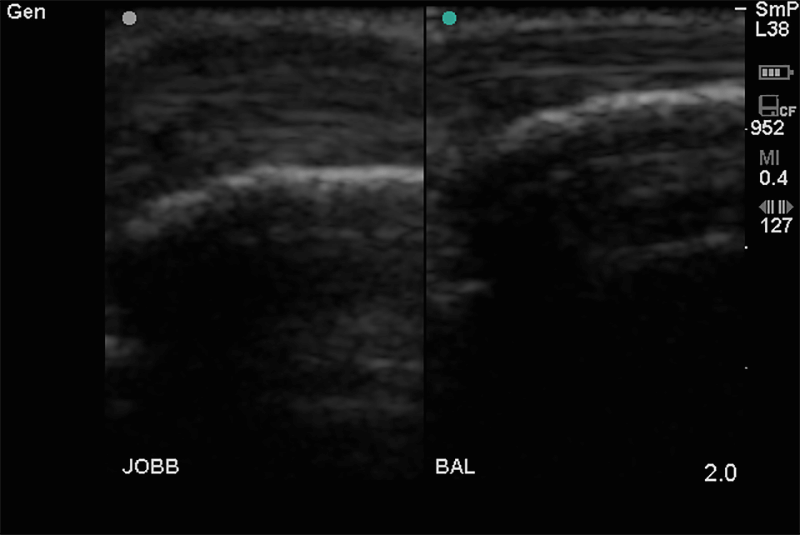

A nyaki, hónalji és ágyéki tájék nyirokcsomóinak gyulladásos vagy daganatos eredetû megnagyobbodásának kimutatására. Ha bármely testtájékon, vagy a felsorolt régiókban fájdalmas vagy fájdalommentes csomó ill. duzzanat jelenik meg, tisztázható, hogy az elváltozás nyirokcsomó vagy egyéb eltérés. Fontos tudni, hogy sok daganat első észlelhető tünete kóros nyirokcsomó megjelenése.